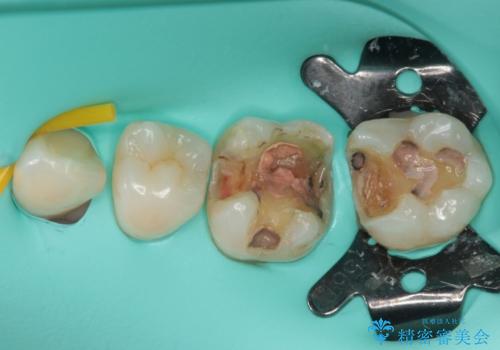

痛みが続いているとのことで、むし歯が神経組織に及んでいる可能性があるため、処置を行うに当たりラバーダムによる唾液の排除を行うこととしました。

手前の歯はむし歯の範囲が広いためオールセラミッククラウンにて、最後方歯は部分的なむし歯であったのでPGAインレー(プラチナゴールドインレー)にて治療を進めることとしました。

仮詰めの状態が良くなかっただけで、むし歯が神経組織にまで及んでいることはなく、無事に治療を終えることができました。